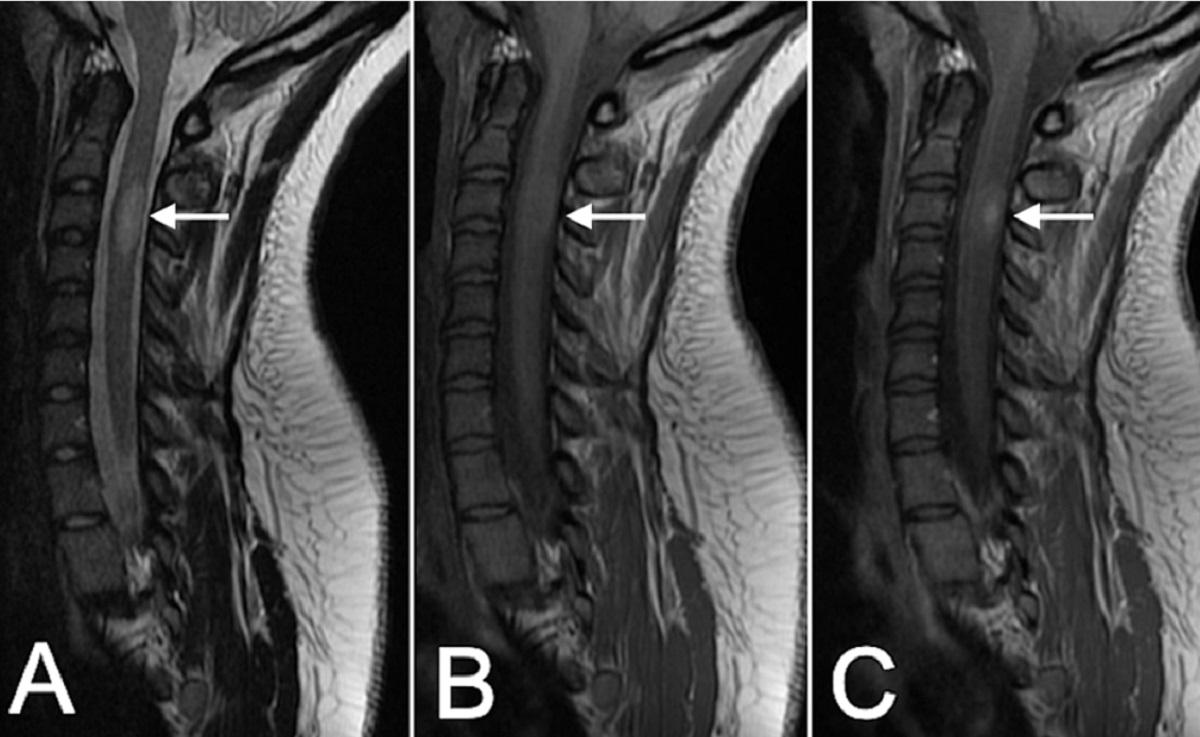

Scleroza multiplă este o boală neurologică inflamatorie cronică în care sistemul imunitar poate afecta mielina care învelește fibrele nervoase. Evoluția și manifestările sunt variabile: unele persoane au perioade de exacerbare urmate de remisiuni, altele un curs progresiv. Există simptome frecvente (oboseală, probleme de vedere, amorțeli, tulburări de mers) și semnale care impun consult imediat, precum pierderea bruscă a vederii, slăbiciunea rapidă a unei părți a corpului sau tulburările acute de vorbire și echilibru.

Cercetarea susține ideea că interacțiunea dintre factori genetici și factori de mediu (infecții anterioare, vit D, fumat etc.) contribuie la risc. Procesele imunologice implică celulele T și B, inflamație și consecințe neurodegenerative. Există tratamente aprobate care pot modifica evoluția bolii, dar multe întrebări rămân: de ce unii răspund bine la tratament, cum se previne progresia pe termen lung și în ce măsură intervențiile complementare pot influența calitatea vieții.